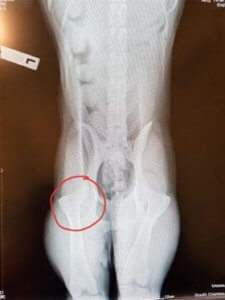

Sasha Newsletter Xray – May (2)

May 24, 2019